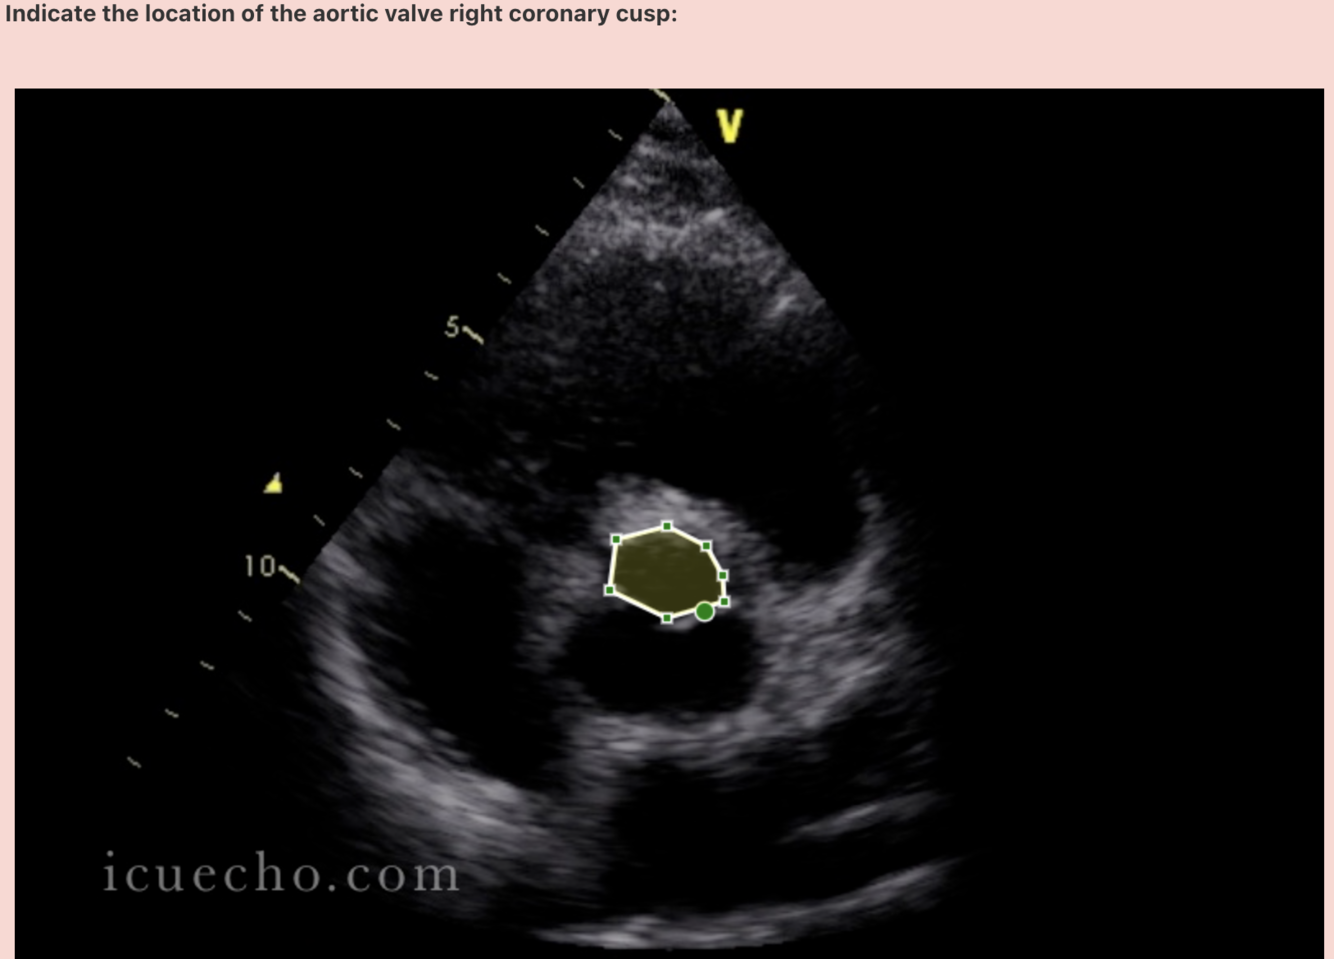

**Answer: right coronary artery**